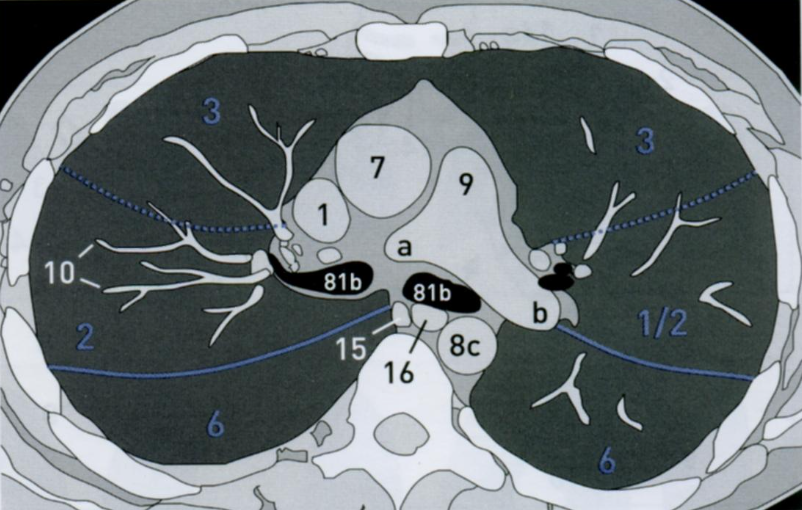

12

Q

КТ грудной клетки №2

Назовите все анатомические структуры, которые Вы знаете, на данном КТ срезе (9).

Найдите грудные позвонки. Затем верхнюю полую вену, восходящую и нисходящую аорту, легочный ствол с легочными артериями, бифуркацию трахеи, непарную вену и пищевод.

A

1 - верхняя полая вена

7 - восходящая аорта

8 - нисходящая аорта

9 - легочный ствол с правой легочной артерией (а) и левой легочной артерией (b)

10 - сосуды

81b - бифуркация

15 - непарная вена

16 - пищевод

Синим цветом отмечены номера сегментов.